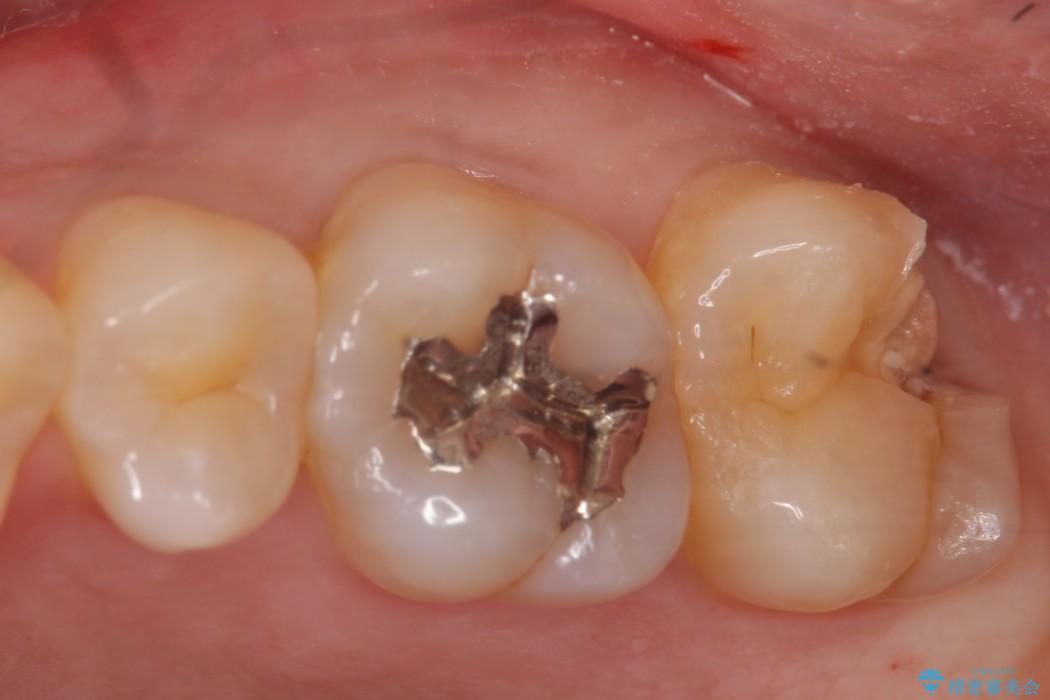

ゴールドインレー

ゴールドインレーはセラミックより強度高く、使用される金合金や白金加金は汚れの付きにくいという特徴を持っており、耐用年数が長いことが特徴としてあります。特に奥歯など強く力が欠けられる箇所に適しています。

反対にデメリットして金属であるため審美性に欠けるという点があります。